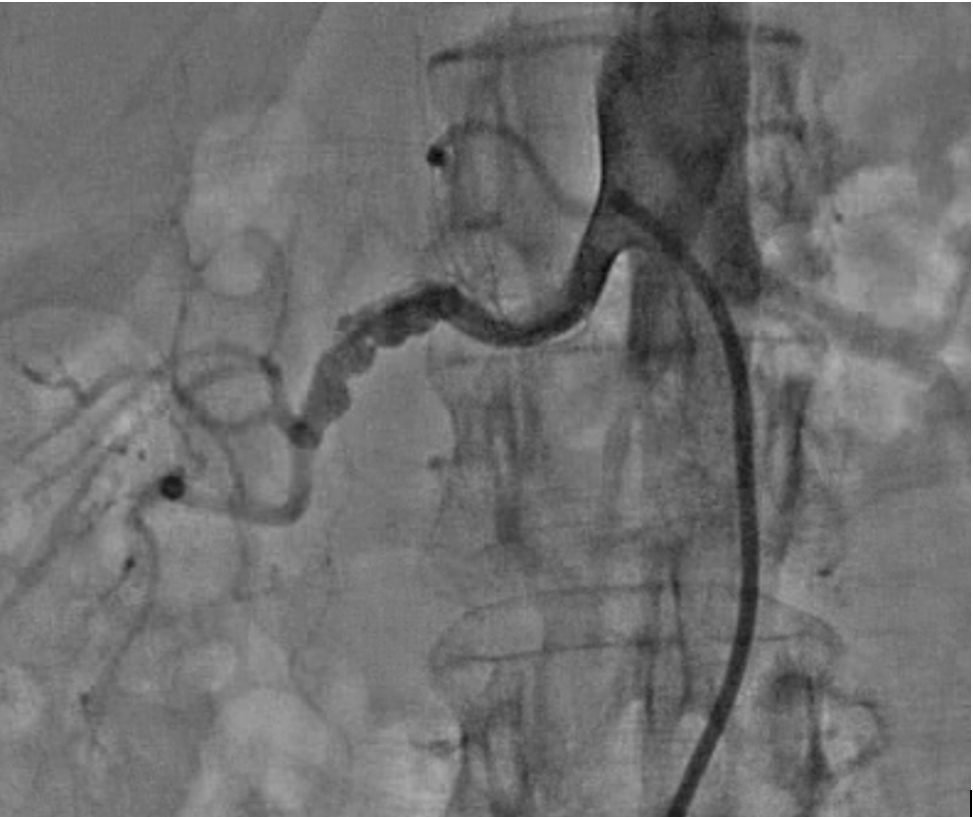

A 58-year-old woman with uncontrolled hypertension on calcium channel and angiotensin receptor blocker and history of left carotid artery stenosis, and carotid endarterectomy at the age of 48 years, was referred cardiac evaluation. Patient’s twin sister had a diagnosis of fibromuscular dysplasia (FMD). Her blood pressure was 190/90 mmHg at presentation. Computed Tomography Angiography (CTA) of the abdomen/pelvis showed a typical nodular stenosis of the mid renal artery consistent with FMD. Patient underwent renal angiogram and successful percutaneous transluminal angioplasty. She still required medical therapy but her BP significantly improved.

Our patient had severe hypertension, carotid artery stenosis and even surgery but had missed FMD diagnosis for > 10 years. Physicians should have a high level of clinical suspicion for young and middle aged women with refractory hypertension and/or artery stenosis, aneurysm, or dissection in any vascular bed. CTA should be performed for renal and carotid artery imaging looking for typical “string of beads” appearance. Cerebral artery aneurysm should also be evaluated. The inheritance pattern for FMD such as PHACTR1 is most consistent with an autosomal dominant trait with variable penetrance. Renal artery angioplasty may lessen the degree of refractory or severe hypertension.